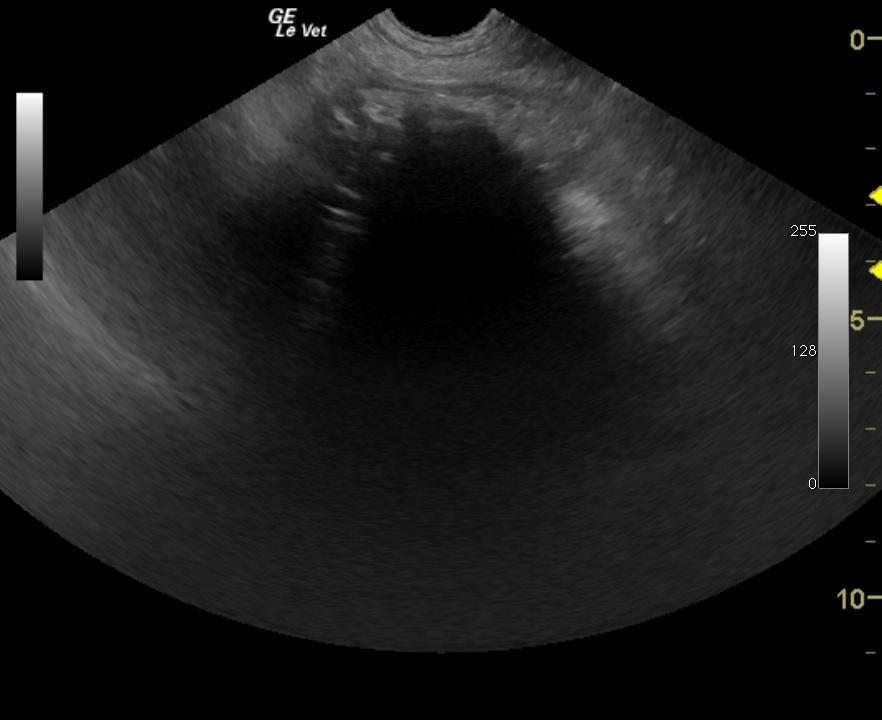

Image 1: Obstruction, severe diffuse intestinal ileus. Image 2: Foreign material, abnormal accumulation of ingesta and focal intestinal stasis

Image and Video 1: Generalized small intestinal fluid dilation. Image and Video 2: Small intestinal focal irregular hyperechoic echo with distal acoustic shadowing.